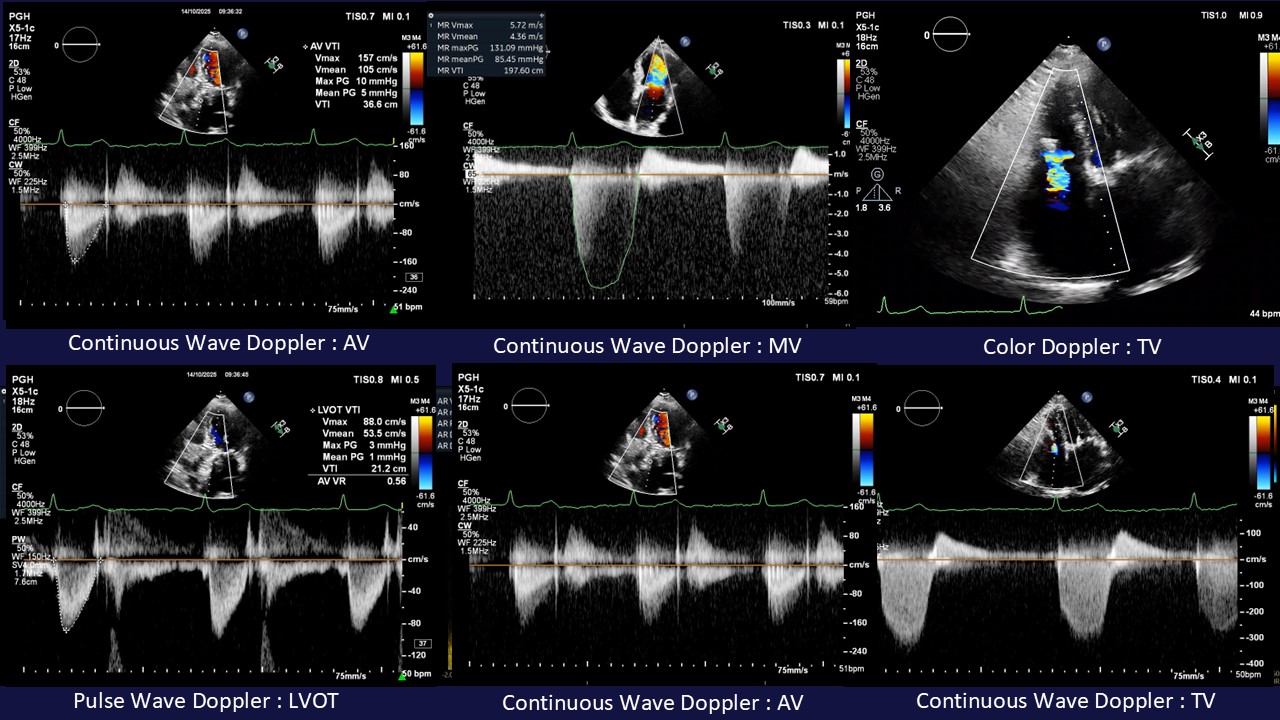

Relevant Test Results Prior to Catheterization

Her ECG revealed AF without pre-existing BBB. Transthoracic echocardiography revealed concentric LVH with 65% of LVEF, severe biatrials enlargement, normal RV function , multiple heart valve abnormalities indicated to a TriClip device with severe TR, moderate functional MR and severe calcific aortic stenosis. As the Heart Team discussion, several cause of symptoms was suspected. We brain stormed to design her individual appropriated-solution, on concerning of natural history in each disease.

Conscious sedation was performed and common femoral artery with 14Fr long sheath was applied. long According to complication concern, we perform FA-TAVR with self-expandable-supra annular THV which'd proper waist for her LCA ostial. After LV-AO gradient assessment of 42 mmHg, we decided to pre-dilated by 20x40 mm. VAC III balloon over 0.035Confida wire. Because of pre-existing TriClip, LV wire pacing was utilized in this case. Self-expandable with supra-annular THV was designed for LCA obstruction, the THV waist and SOV diameter were evaluated appropriately along with LCA height, and Cusp over view (RAO17, CAU32) for avoid BBB was used. Although her had low AV calcium, but small LVOT was not be additional risk factor for THV embolization because. Improvement of LV-AO pressure gradient reduction to 4-5 mmHg., trivial paravalvular leak, significant MR and TR reduction were detected after finished procedure. Application of 2 Proglide vascular closure devices assisted puncture site complication was disappear. The patient went out from hospital in next 72hr. later, clinical NYHA II without early complication, transthoracic echocardiography revealed appreciated result for THV implantation. Further that, significant reduction of MR and TR were good predictor for overall long term result. However, concerned-valvular condition had remained in chart, especially progression of secondary MR from atrial fibrillation that might be adjusted by another TEER. Life-long DOACs also be applied.